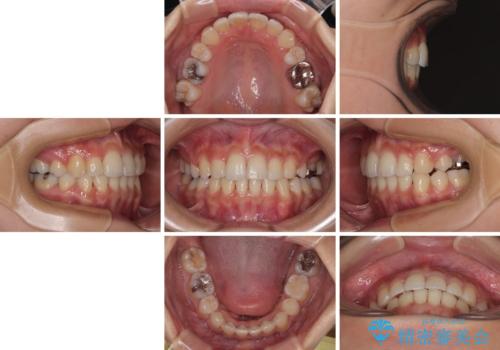

【モニター】閉じにくい前歯とクロスバイト ワイヤー装置での抜歯矯正

- 前歯のクロスバイトと口元の膨らんだ横顔の印象を気にして来院された患者様です。

ご本人の気にされている口元は、分析数値からするとそれほど突出しているものではありませんでした。

しかしながら。そのまま叢生を解消すると横顔が突出した印象になる可能性が高かったため、上下左右の小臼歯4本を抜歯して、ワイヤー装置にて矯正治療を行うこととしました。

上下左右の第一小臼歯4本を抜歯して治療を行うことがセオリーでしたが、左下は第二小臼歯が銀歯であったため、イレギュラーではありますが、そちらを抜歯しました。

その影響で治療期間は長くなりましたが、処置していない歯を保存することができました。